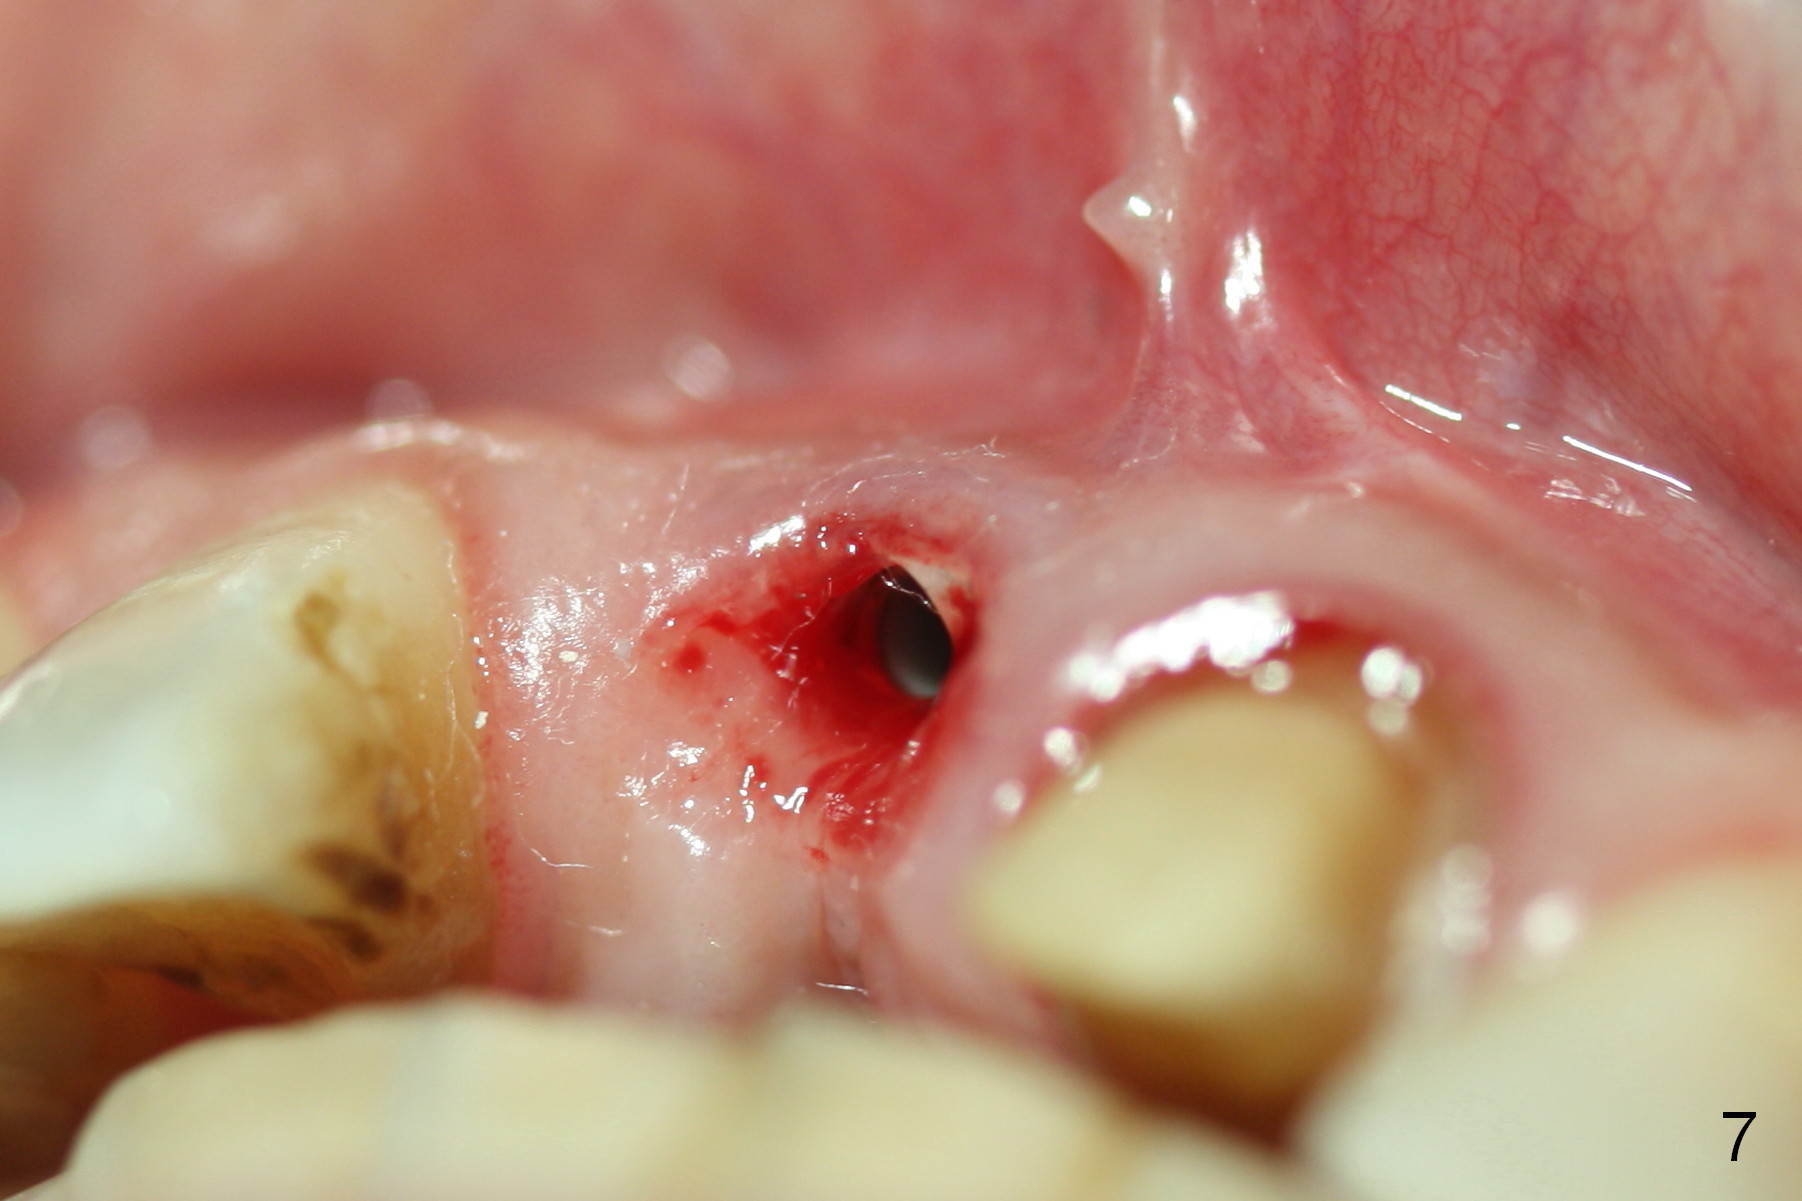

Fig.6,7 were taken a month ago when the Zirconium abutment was fractured, showing the position of the coronal end of the implant. To retrieve the abutment, an envelop incision will be made (Fig.8) with elevation of the buccal flap for the best visibility. Prepare abutment removing drivers (x3) and try in vitro. To improve cosmetics, the implant/bone segment seems to be required to be lingualized ~3 mm (Fig.9 arrow) with bone graft buccally (red circles, possibly chin graft).